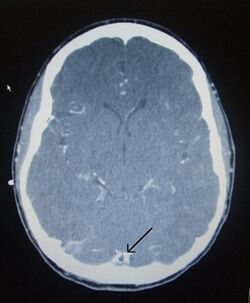

CT venogram showing a filling defect in the sagittal sinus (black arrow)

A dural venous sinus thrombosis of the transverse sinus. Greater on the right than left.

There are various neuroimaging investigations that may detect cerebral sinus thrombosis. Cerebral edema and venous infarction may be apparent on any modality, but for the detection of the thrombus itself, the most commonly used tests are computed tomography (CT) and magnetic resonance imaging (MRI), both using various types of radiocontrast to perform a venogram and visualise the veins around the brain.[3]

Computed tomography, with radiocontrast in the venous phase (CT venography or CTV), has a detection rate that in some regards exceeds that of MRI. The test involves injection into a vein (usually in the arm) of a radioopaque substance, and time is allowed for the bloodstream to carry it to the cerebral veins – at which point the scan is performed. It has a sensitivity of 75–100% (it detects 75–100% of all clots present), and a specificity of 81–100% (it would be incorrectly positive in 0–19%). In the first two weeks, the "empty delta sign" may be observed (in later stages, this sign may disappear).[11] The empty delta sign is characterized by enhancement of the dural wall without intra-sinus enhancement.[6]